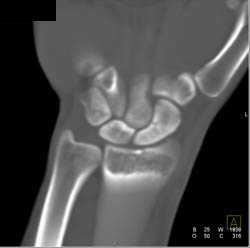

Thigh Swelling and Amputated But Reimplanted Toes